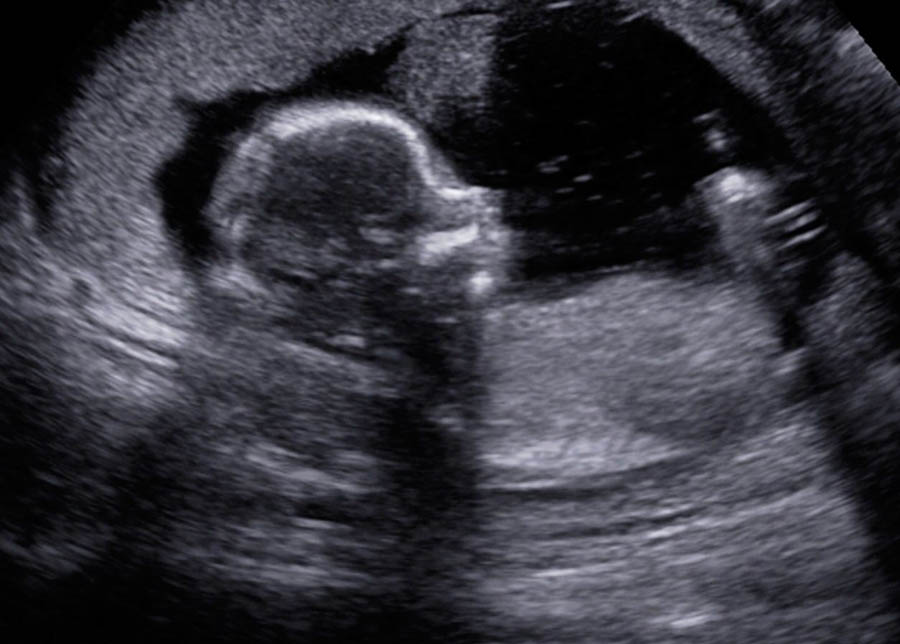

An operator contacted Cindy Amos, nurse manager for The Resource Center in the Greeley, about 30 miles from Fort Collins. Leslie went to the center and Amos began the APR protocol – conducting an ultrasound to see if the woman’s pregnancy was still viable and then administering progesterone.